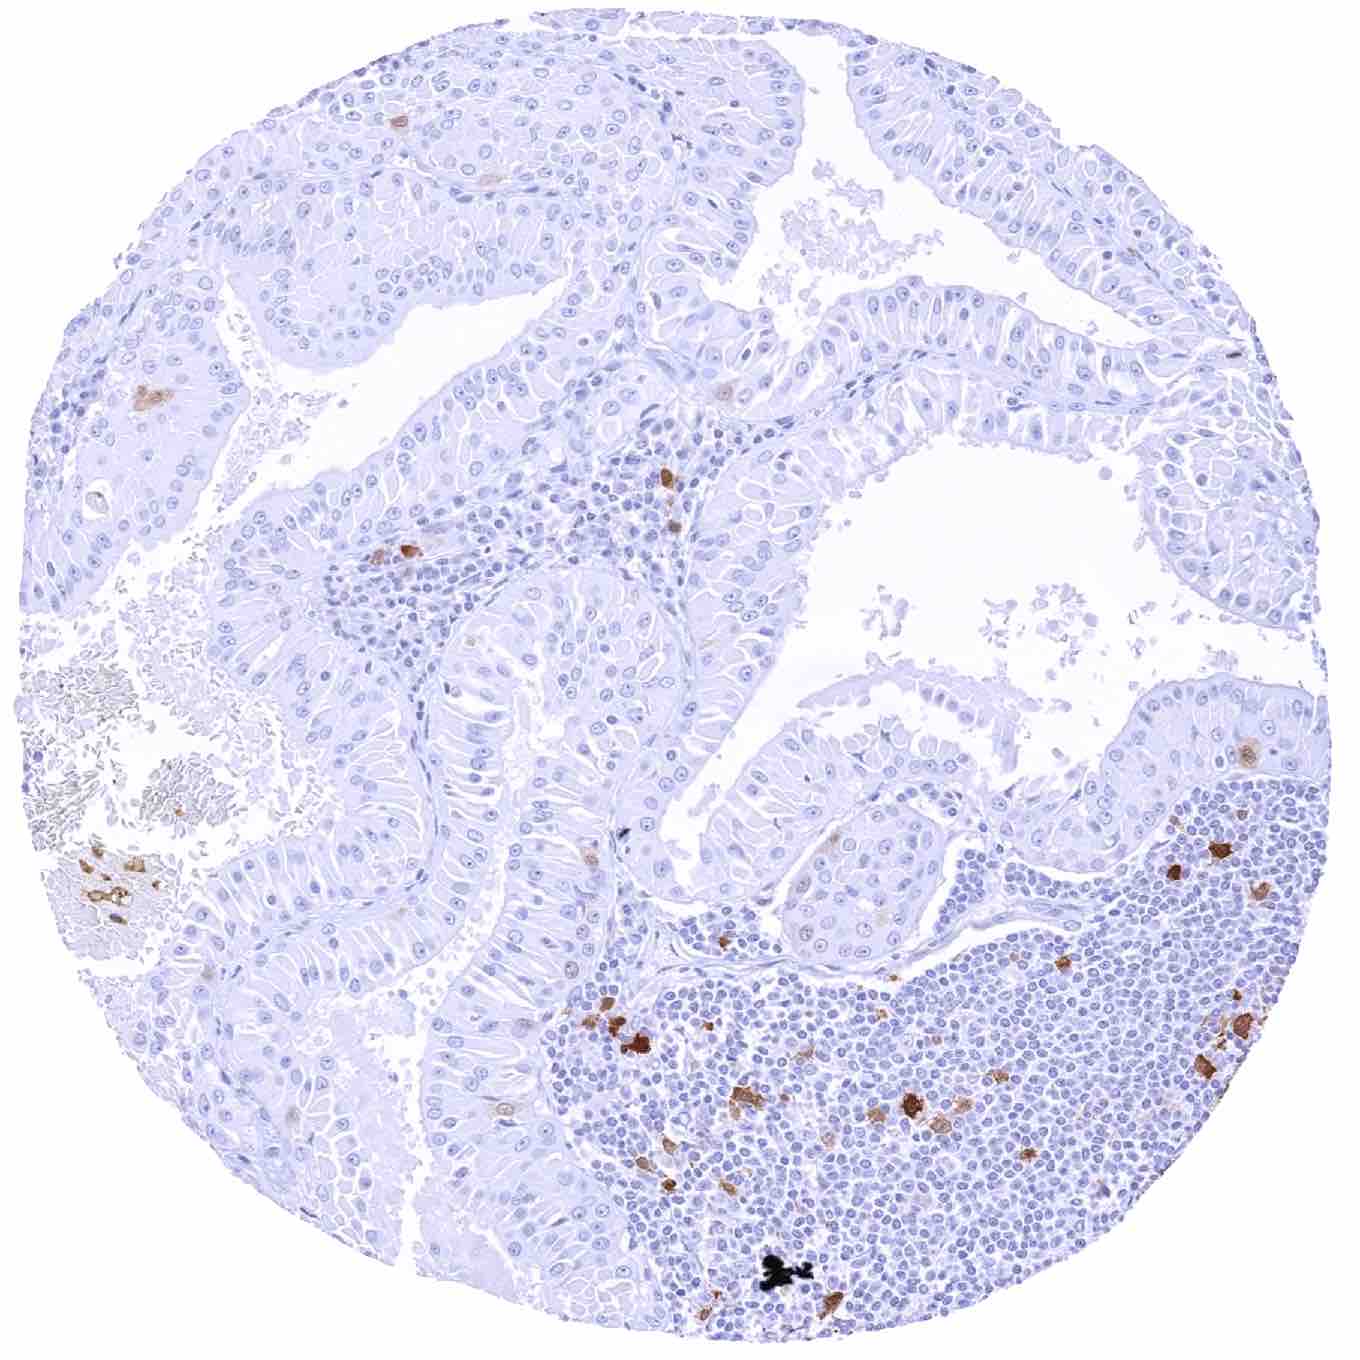

Colon – TYMS negative colorectal adenocarcinoma. TYMS staining is only seen in some inflammatory cells